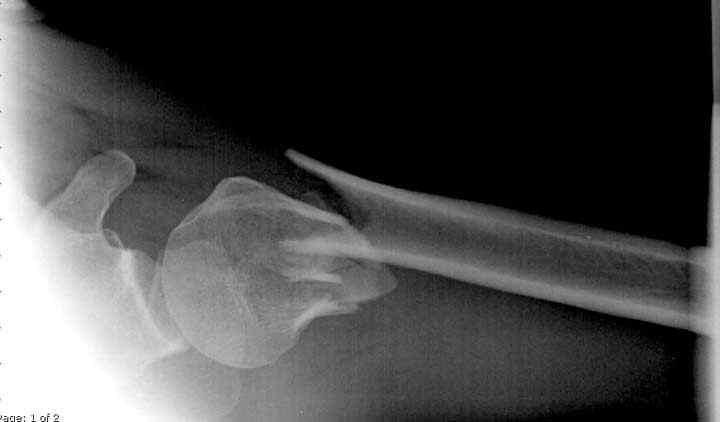

Здесь пример открытой репозиции 57 летнего с переломом плеча (1,2)  смещение обнаружено на  интероперационном снимке. При нормальной прямой проекция (3) угловое смещение обнаружили в аксиальной проекции (4)